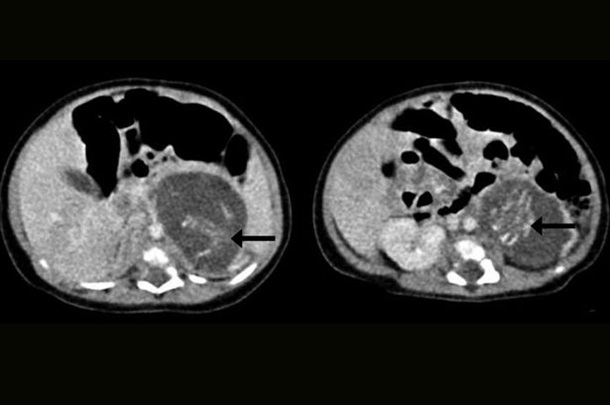

У підсумку тритижневої дівчинці зробили операцію: між печінкою і ниркою хірурги виявили два плоди. Один з них важив 9,3 грама, інший - 14,2 грама, що відповідає приблизно восьмий і десятому тижні вагітності. У обох немовлят знайшли пуповину, з'єднану з плацентоподобной масою в животі дівчинки.

Фото: Hong Kong Medical Journal

УЗД плода